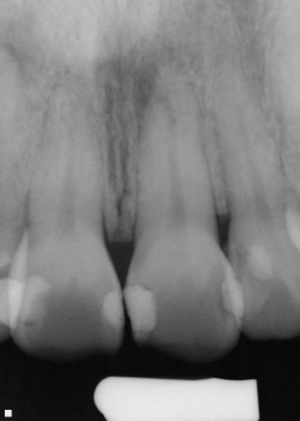

After

Root canal therapy is required when the dental nerve is damaged. In a healthy tooth, blood vessel, nerve and lymphatic systems are all present inside a hollow tube inside the tooth. When a tooth is diseased, all the dead tissue must be removed, cleaned and sealed. The success of a root canal treatment depends on the perfect hermetic seal of the tooth on both ends.

The success rate of modern root canal technique is very high. However, due to variations in shape of teeth, sometimes failures can occur; although at very low percentage.